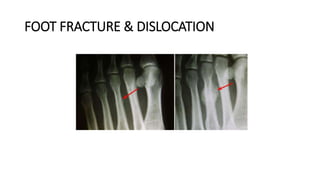

FOOT FRACTURE & DISLOCATION

DEFINITION

• Fractures of the toes and forefoot are quite common. Fractures can result from a

direct blow to the foot—such as accidentally kicking something hard or dropping

a heavy object on your toes.

• They can also result from the overuse and repetitive stress that comes with

participating in high-impact sports like running and basketball.

• Although fracturing a bone in your toe or forefoot can be quite painful—it rarely

requires surgery. In most cases, a fracture will heal with rest and a change in

activities.